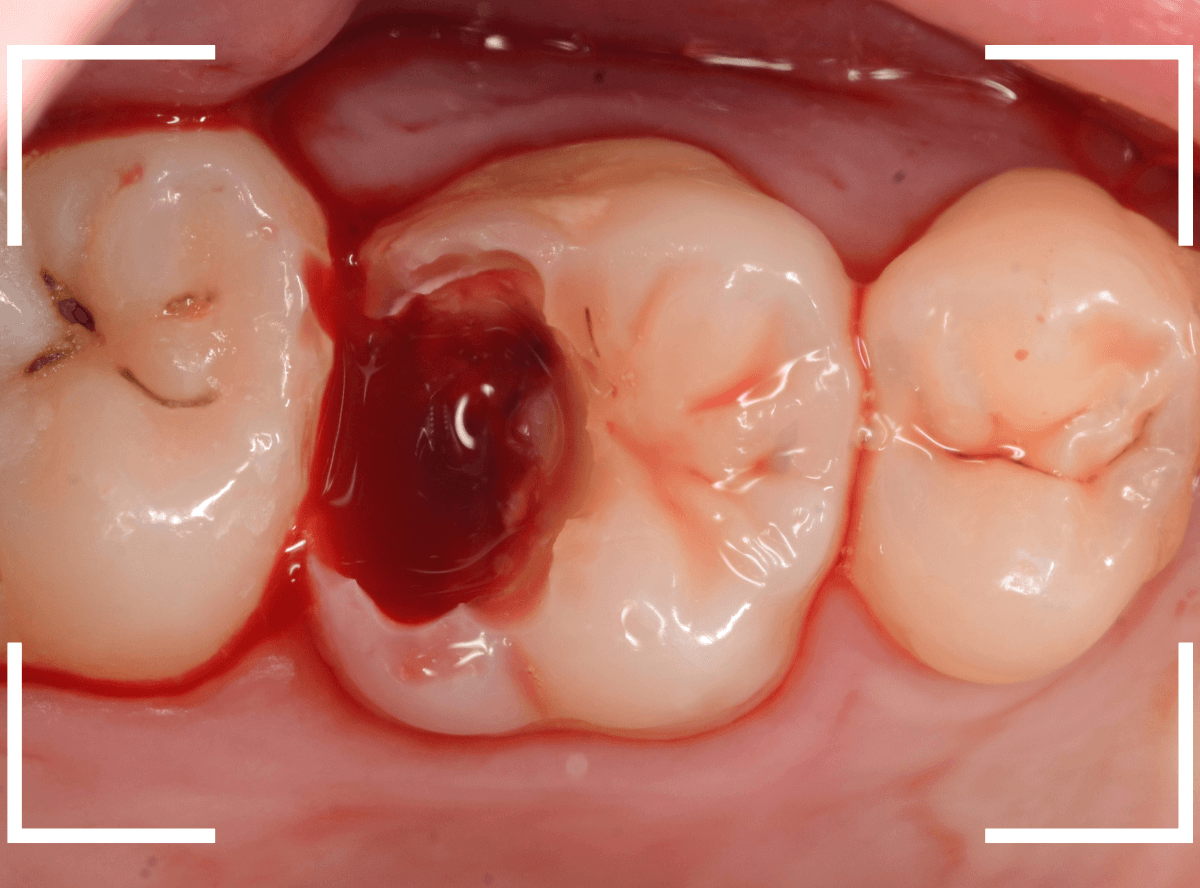

麻酔をして、治療を開始します。

レジンを外すと、中から出血してきました。

これは、歯のスキマに歯肉が入り込んでしまったために起こってしまったものです。

おそらく、随分前から虫歯が進行していたと思われます。

止血しながら、電気メスで歯の中に入り込んだ歯肉を除去します。

虫歯と入り込んだ歯肉でぐちゃぐちゃになっている状態でした。

これでは、痛みが出てもおかしくありません。